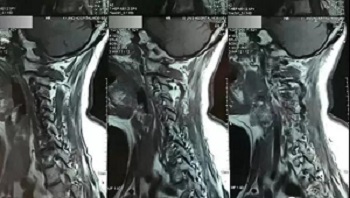

(区域7)

(区域8)